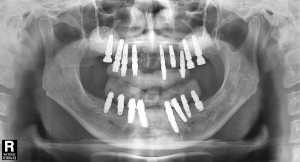

최종 보철물까지 올리고 난 후 구강 내 사진입니다.

평상시의 교합 뿐만아니라 좌우로 아래턱을 크게 움직였을 때도 불편함이 없습니다.

이후 환자분은 정기적으로 체크를 받고 계시고

이전에 좋지 않았던 구강위생도 계속적인 구강위생교육으로 많이 개선되었습니다.